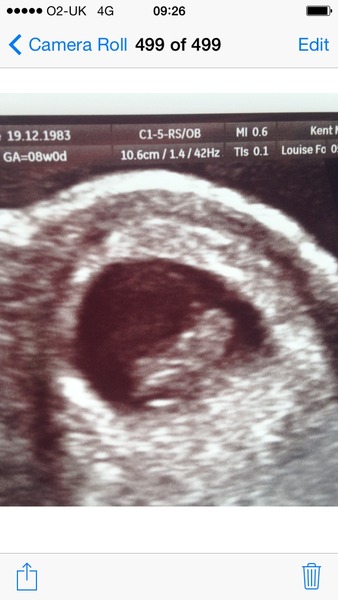

So had my early scan today and pleased to say all is well! Such a clear picture perfect heartbeat and perfect size for 8 weeks! My lovely little bean even wriggled for us and saw it's little stumpy arms was so nice to see! Have tried to attach a pic so hopefully it comes through.

What a lovely pic littlemiss! Amazing isn't it :)

Ah thats a fab pic, I cannot wait for my next scan!

Welcome huffle and pillow. Great scan pic littlmiss.